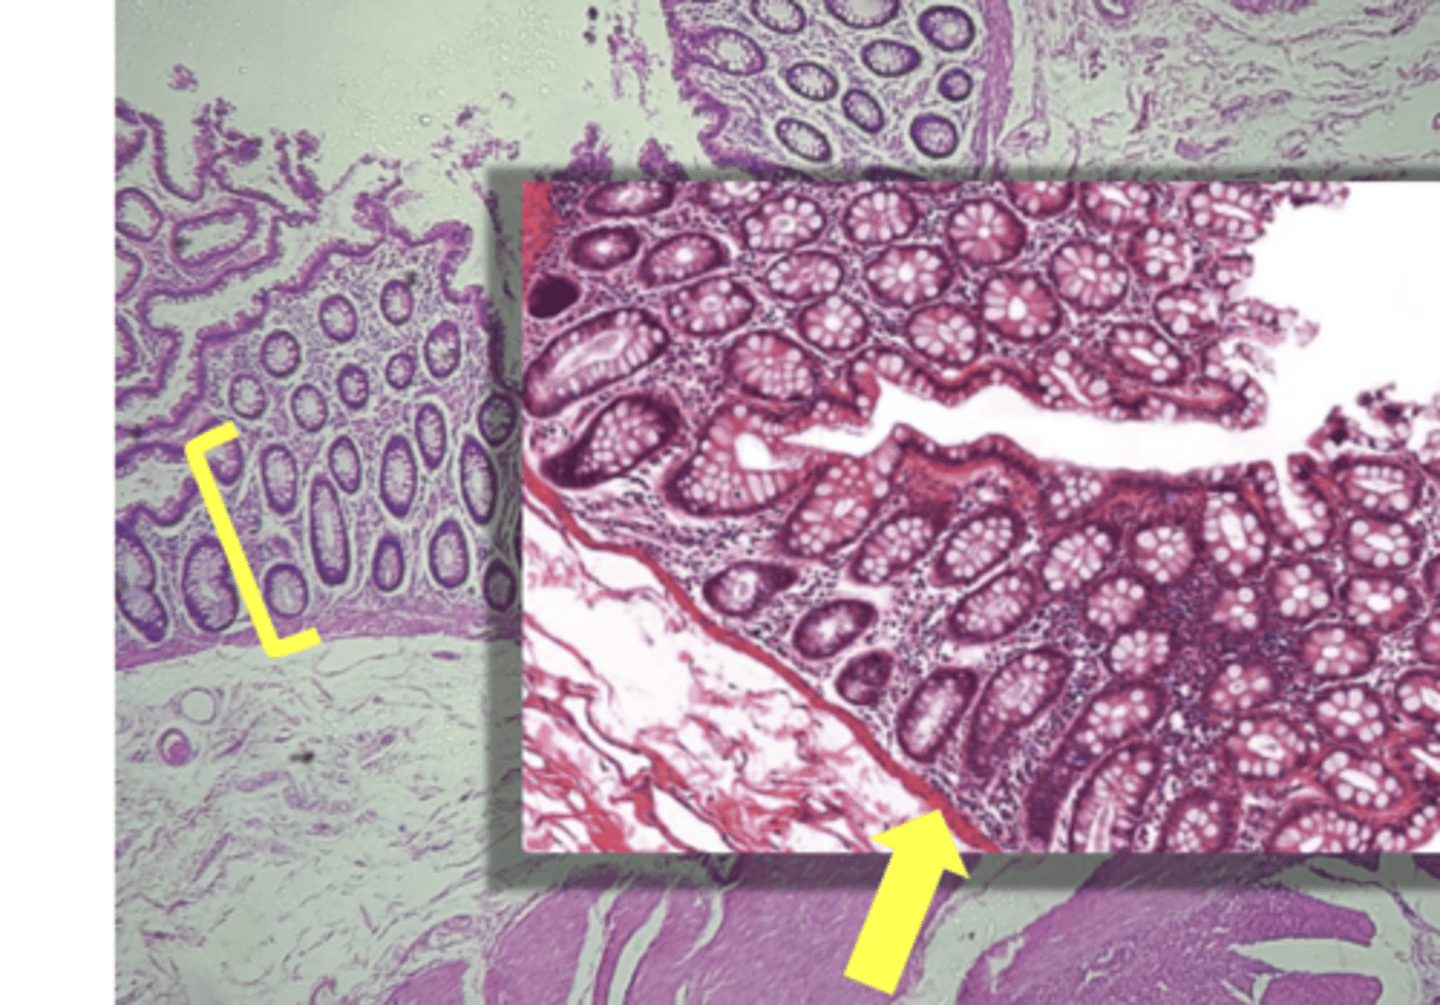

colon- large intestine

name the tissue

circular layer

(Lg. intestine)

longitudinal layer

mucosa

(lg intestine)

Submucosa

muscularis externa

goblet cells-mucus (LARGE # KEY CHARACTERISTIC)

name the cell & what it secretes

intestinal crypts

muscularis mucosae